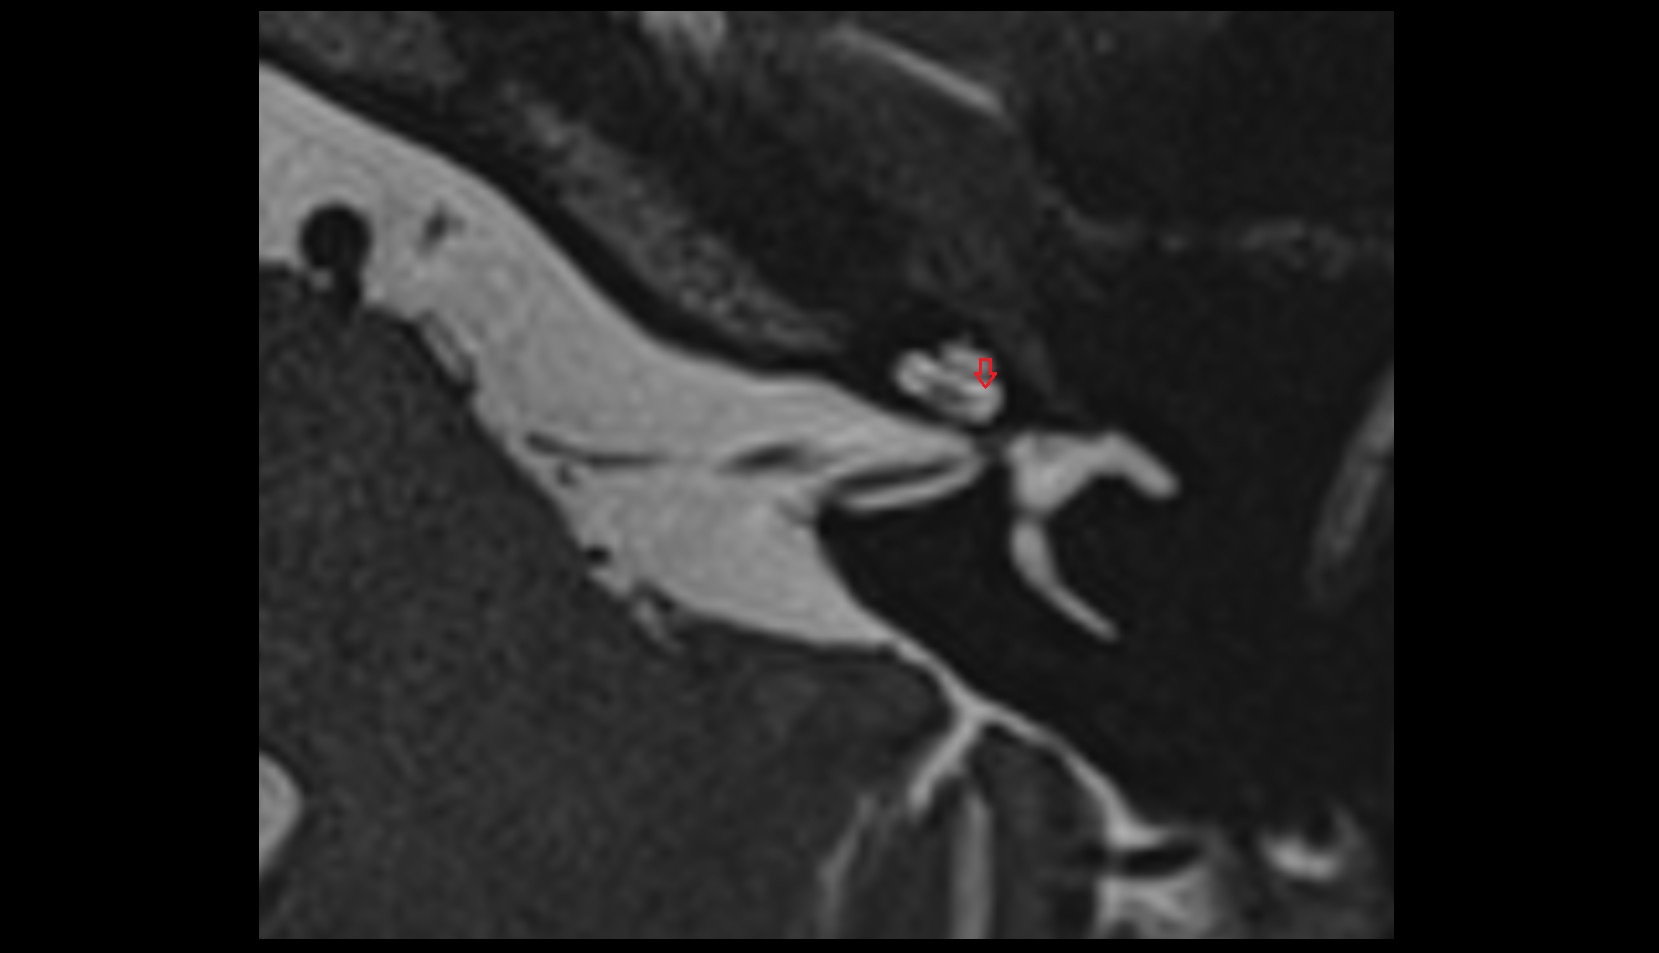

- Temporomandibular joint

- Mandibular condyle

- Mandibular fossa

- Articular disc of temporomandibular joint

- Articular eminence